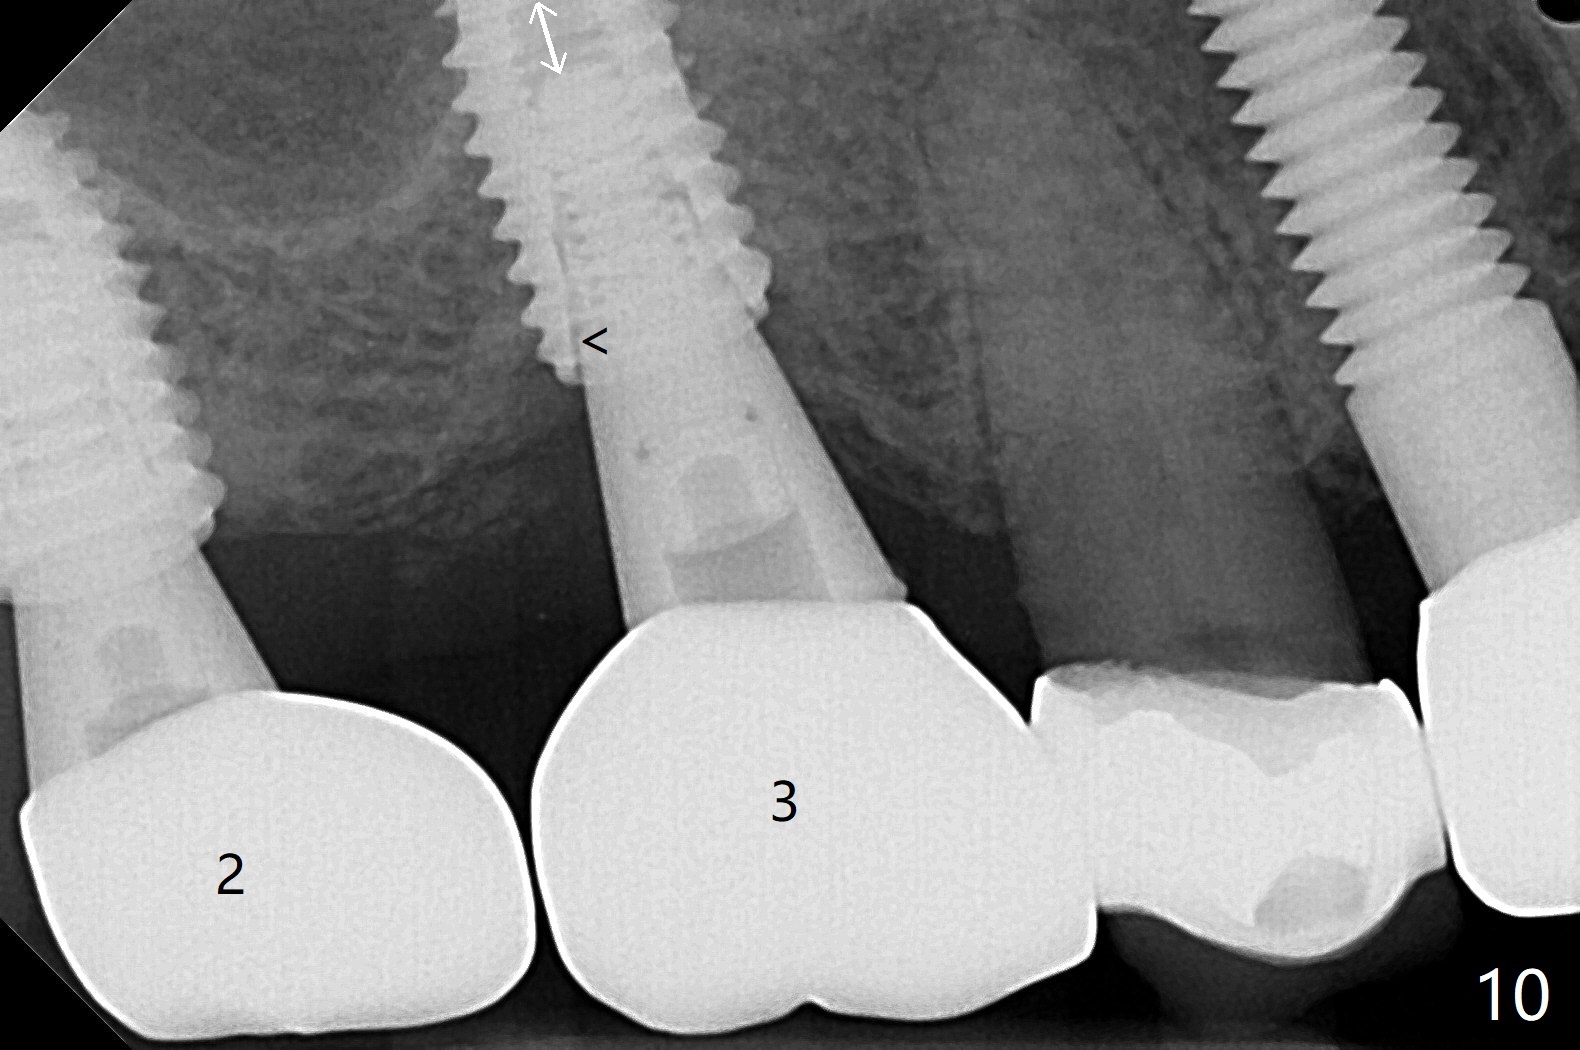

Osteotomy at the sites of #2 and 3 goes on as planned. Sinus lift using DIO 2.8 mm round bur with 6 and 7 mm stoppers (respectively) is carried on without certainty, because it is difficult to feel the stop through the osteotomy. The crest may be uneven or soft. It appears that the soft tissue landmark as a stop may be easier to identify. In fact a 3 mm IBS Magic Expander (an osteotome) was used for sinus lift at #3. The 2 implants are placed with 20 and 30 Ncm (Fig.1,2). Healing abutments are inserted. At 2-week follow-up, the patient reports "pain a few days earlier, took a pill of antibiotic, pain gone. UR metal is sharp". She does not take antibiotic regularly. Exam reveals that there is heavy plaque around #2,3 healing abutments. The buccal edge of #2 abutment is trimmed for comfort. Nearly 1 month postop, #3 healing abutment dislodges with buccal gingival erythema and edema with purulent discharge (Fig.3). Healing screw is placed at #3 with Amoxicillin and Chlorhexidine prescribed. One week later, the implant at #3 turns when the healing screw is retightened (Fig.4). After debridement, Vanilla graft is placed. There is no infection at #2 or 3 four months postop (Fig.5,6); the lingual gingiva is erythematous and edematous at #29 with mobility II (Fig.7 (vertical root fracture)). Uncover is conducted at the site of #3; there is no infection superficial 7.5 months postop (Fig.8). There is a large buccal defect upon incision with dark hemorrhage. In fact the bone density is low crestally (Fig.8 *). Bone graft is placed for the 2nd time. Eleven months later (1.5 years post implant placement), the bone regrows crestal (Fig.9 *). The crown at #3 is loose 1 year 5 months post cementation (Fig.10). After proximal trimming (Fig.11 *), the abutment at #3 is seated completely. After lab repair, crown oral cement, crown/abutment removal for excess cement removal, the crown/abutment cannot be torqued >25 Ncm (Fig.12, 30 Ncm). PA shows incomplete seating (Fig.12 <). Then the crown is sectioned so that the abutment has more freedom to be seated completely with pressure against the gingiva (the patient feels pain, Fig.13). Torque is 30 Ncm. After crown cementation, the abutment will not be removed for cement removal.